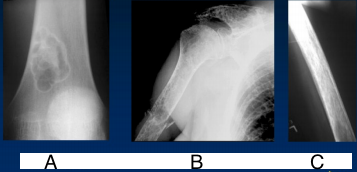

| What disease is this? What is shown by A, B and C? | Psoriatic arthritis. A = destructive changes B = Pencil in cup deformity C = IPJ fusion |

| Describe the patterns of destruction in A, B, C. Which is more malignant? | A = geographic destruction B = moth eaten destruction C = permeative destruction Malignancy = C>B>A |